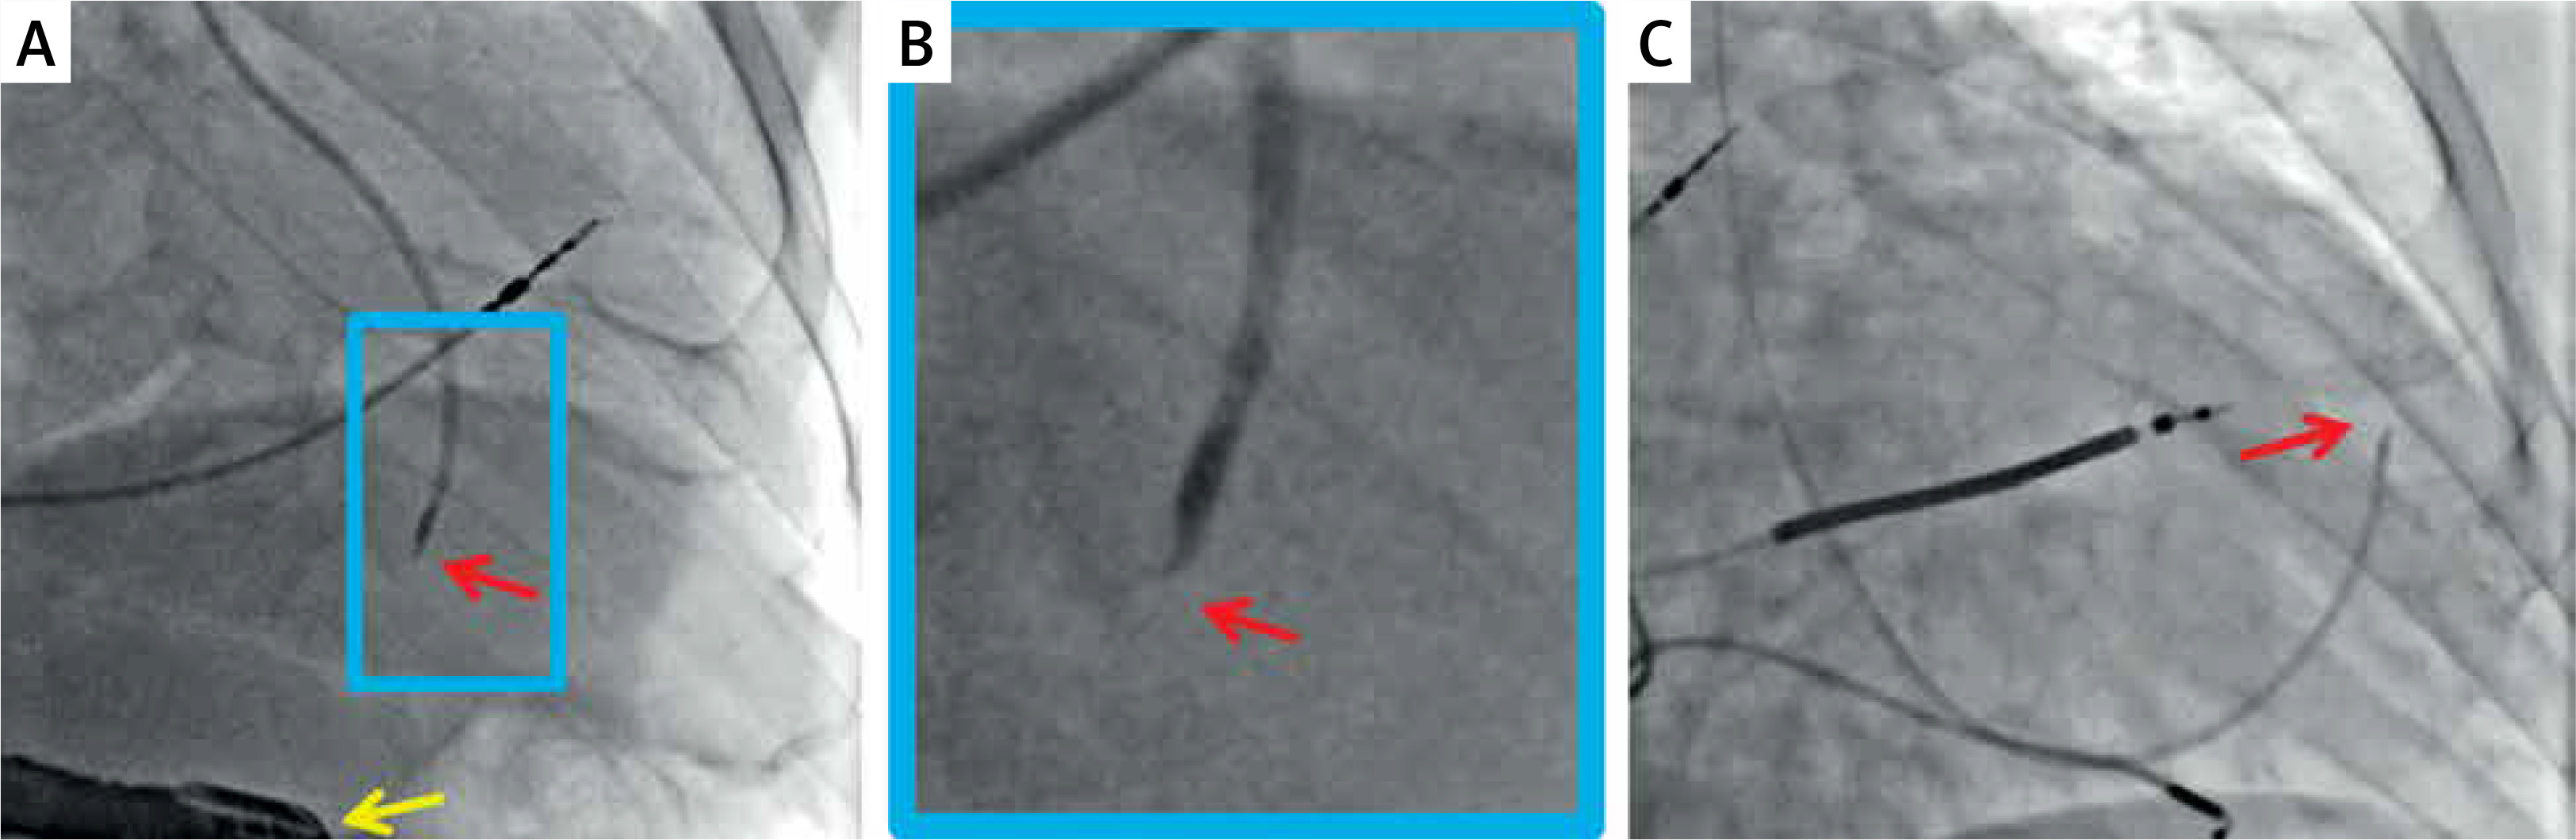

The idea to directly implant cardiomyocytes into the injured area was initially tested in animal models. Contrary to adult cardiomyocytes, which did not survive under any conditions, fetal and neonatal cells formed new and mature myocardium in inbred rats [25]. The procedure can be done either under direct vision, usually using minimally invasive surgical access (Figure 1 C) or percutaneously (Figure 2).

Figure 2

Typical radiographic images of percutaneous trans-endocardial delivery of stem cells using a dedicated, steerable catheter with a curved needle (red arrow) that has an adjustable length and possesses side holes. Effective anchoring of the needle in the target site is confirmed with a minimal contrast injection. The delivery is performed to pre-specified myocardial segments (based on their viability and thickness) under transesophageal echo control (A, yellow arrow) or using an LV-gram-based myocardial map integrating information from echocardiography and/or magnetic resonance imaging (C). Examples show standardized cell suspension (cocktail with pro-angiogenic factors) delivery to a pre-specified site in the inferior wall (A) and anterior wall (C). B is a close-up of A. The delivery occurs independently of the cardiac cycle (i.e., throughout systole and diastole). Images courtesy of Prof. Piotr Musialek and Dr. Adam Mazurek